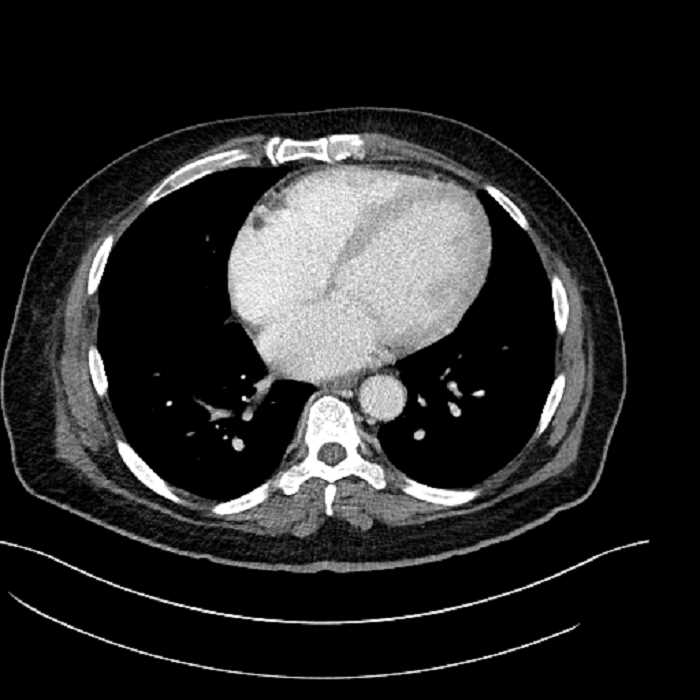

Age: 63

Sex: Male

Indication: Abdominal pain

• Lower chest

• Mild cardiomegaly

• Mild dependent atelectasis

Acute sigmoid diverticulitis complicated by a small contained perforation and a large abscess in the right hepatic lobe. Additional small subcapsular abscesses along the anterior margin of the left hepatic lobe.